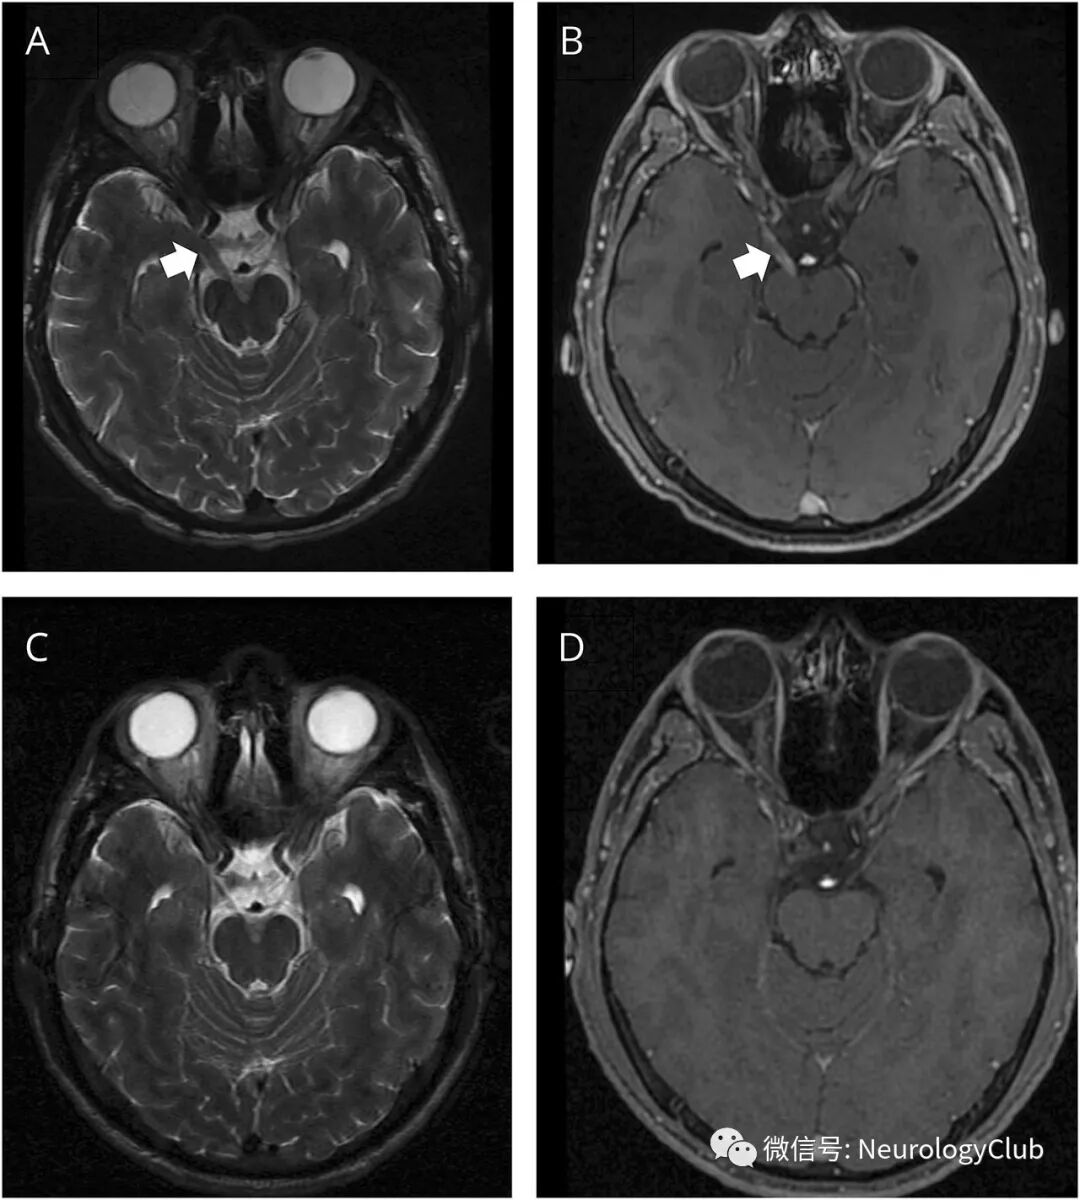

29岁HIV感染男性,接受抗逆转录病毒治疗,病毒载量为阴性,CD4+T细胞计数低(344/mm3),表现为右眼睑下垂和复视。查体可见右侧瞳孔扩大,对光或调节反射消失。除外展外,其余各个方向眼外肌活动受损。MRI可见右侧动眼神经增粗并强化(图A-B)。

(图:A:T2WI可见右侧动眼神经脑池段弥漫增粗;B:增强T1可见病灶明显强化;C-D:4月治疗后T2WI和增强T1可见病灶影像学较前完全好转)

血清性病研究实验室(VDRL)和梅毒螺旋体血凝反应(TPHA)检测阳性(滴度分别为1/512和1/10,240),在脑脊液中进一步证实:VDRL阳性,TPHA滴度1/320,单核细胞数92/μL,蛋白55mg/dL,糖正常。患者接收2周的青霉素治疗,复查影像学完全好转(图C-D),临床部分恢复。